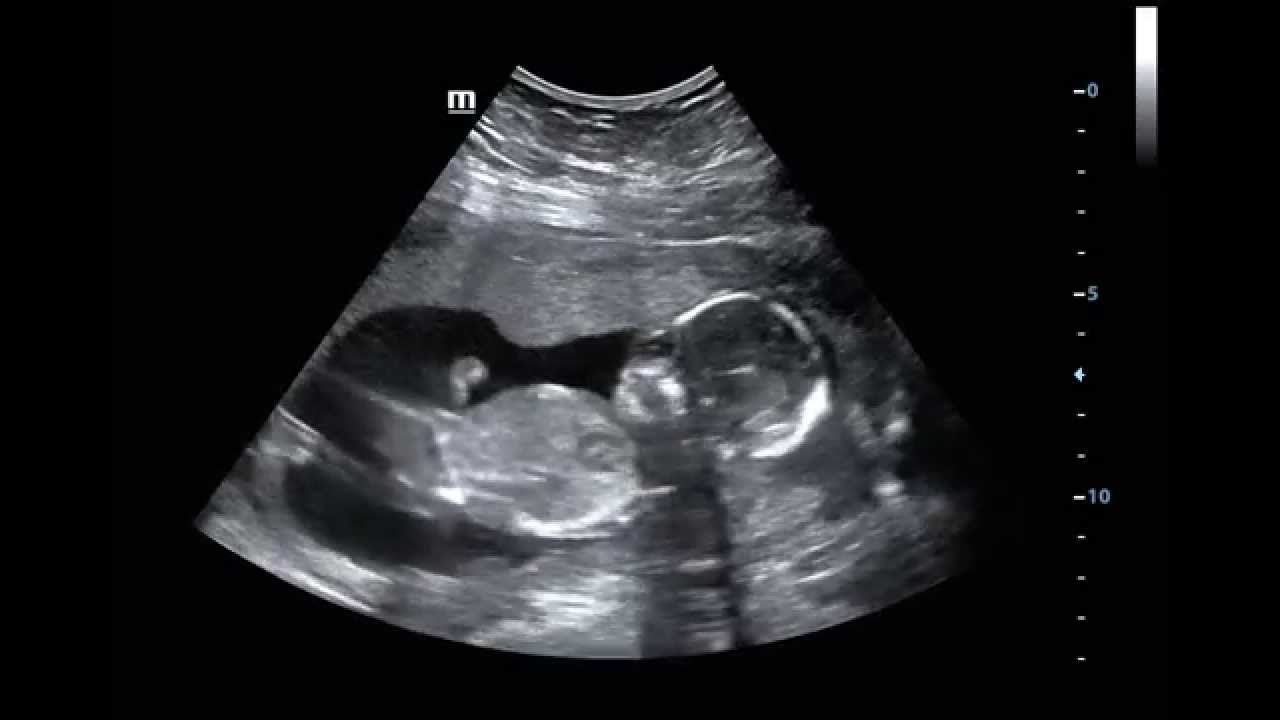

WebAbout Press Copyright Contact us Creators Advertise Developers Terms Privacy Policy & Safety How YouTube works Test new features Press Copyright Contact us Creators ... WebEl ecocardiograma fetal inicial suele realizarse entre las semanas 18 y 22 de gestación y puede repetirse según sea necesario a lo largo del embarazo. El estudio inicial suele. WebEn la semana 17 de embarazo el feto alcanza un tamaño medio entre 12-16 cm, y un peso aproximado de 100 gramos. PUBLICIDAD. La posición habitual es semiflexionada, con.

ECOGRAFÍA 17 SEMANAS DE GESTACIÓN, EMBARAZO 17 SEMANAS, SEMANA 17 DEL EMBARAZO, FETO 17 SEMANAS